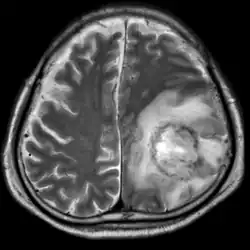

| T2-weighted MRI showing a necrotic brain abscess caused by Acanthamoeba. | |